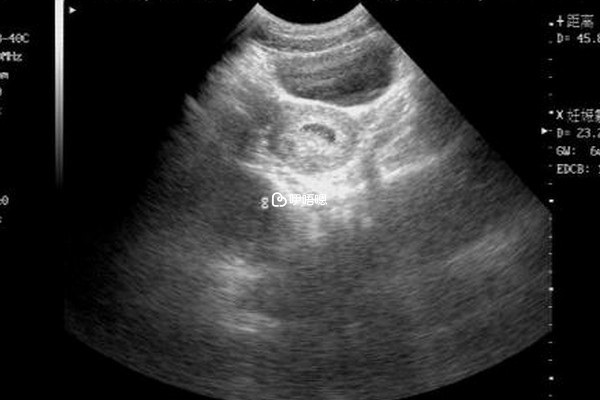

現在的明文規定醫生是一定不能告訴父母孩子的性別的,而且因為我們中國家庭絕大多數還是想有兒子傳宗接代,就是怕一些父母因為懷了不是兒子,而去打胎,或者家庭關係出現裂痕等等不良情況,但有些醫生又迫於家長對於孩子性別的逼問,只能通過一些暗語來暗示,胎兒頭大腿短是不是暗示生兒子可以看看其他媽媽的經驗: